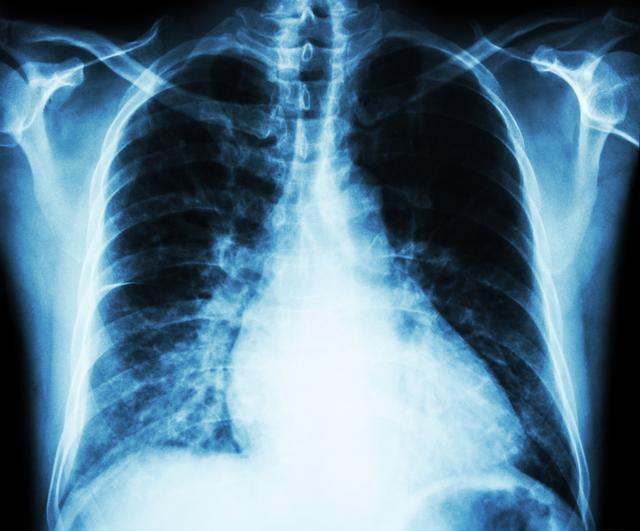

肺磨玻璃结节其实是个影像学概念,是指在胸部CT检查时发现的肺部表现为密度轻度增高的云雾状淡薄影/圆形结节,样子像磨砂玻璃一样,其内支气管及血管纹理仍可显示,所以称之为磨玻璃结节。肺部结节分为实性结节,纯磨玻璃结节和部分实性磨玻璃结节。实性结节恶性可能性最低,磨玻璃结节恶性概率高于实性结节,部分实性结节恶变率高于纯磨玻璃结节。磨玻璃结节并不一定是癌,也不是所有磨玻璃结节会转变成癌,约有1/3磨玻璃结节会消失,1/3会长期不变,1/3会转变成癌。磨玻璃结节可以是很多病变导致的,比如炎症,比如非典型腺瘤样增生,也可能是肺出血、肺泡炎CT上表现为磨玻璃样病变。

>20 mm的磨玻璃结节恶性率有80%;CT上结节表现为分叶征、毛刺征、胸膜凹陷、部分实性;贴近脏层胸膜的周围型磨玻璃结节。还有一些磨玻璃结节动态观察发现结节增大或者实性成分增加也要警惕恶性可能。

即便磨玻璃结节怀疑恶性,也不会是晚期肺癌转移,因为肺癌和肺内转移灶,一般会有主病灶和多发卫星病灶,主病灶会比较大,转移灶小且多发,肺内转移灶在CT上一般为不规则结节,不会表现为磨玻璃结节。但多发磨玻璃结节有可能是多灶早癌,也就是说都是原发性主病灶,发展时期不同,有的已经是原位癌,有的仍在不典型增生阶段。